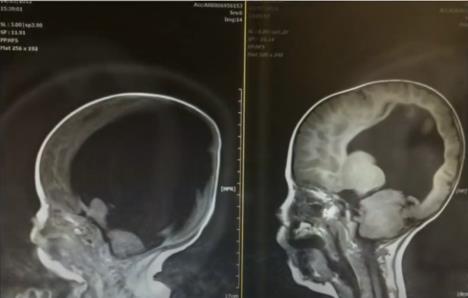

Ali to nije bilo sve. U materici, cista u njegovom mozgu uništila je skoro celokupno moždano tkivo. Ultrazvuk je pokazao – Noa je imao samo 2% mozga. Lekari su upozorili njegove roditelje da možda neće moći da zatvore rupu u njegovim leđima i da će njegov život, ako se rodi živ, biti ispunjen patnjom.

Noa je rođen 6. marta 2012. godine carskim rezom. Njegova glava je bila abnormalno velika zbog hidrocefalusa – nakupljanja tečnosti koje vrši opasan pritisak na mozak. U prvim satima njegovog života, lekari su morali da izvrše dvostruku operaciju: zatvorili su mu rupu na leđima i umetnuli šant kako bi odveli tečnost iz mozga.

Godine su prolazile, i umesto da ostane nepokretan i nesposoban da govori, Noa je počeo da postiže neverovatne stvari. Do šeste godine, skeniranje je pokazalo da je njegov mozak razvijen 80%. Naučnici i lekari nisu mogli da daju definitivno objašnjenje.